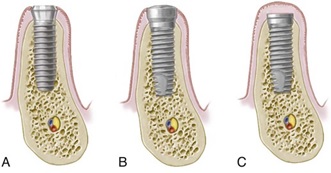

روش یک مرحله ای:

در این روش بیمار فقط یک جلسه جراحی خواهد داشت و جلسه دوم جراحی حذف خواهد شد.بدین ترتیب که قطعه هیلینگ اباتمنت طی جراحی مرحله اول روی فیکسچر بسته میشود و بعد از ۲-۳ ماه ایمپلنت مستقیما آماده قالب گیری است. در این روش باید بیمار استخوان مطلوبی داشته و متخصص ایمپلنت هم مهارت کافی جهت این تکنیک را داشته باشد.